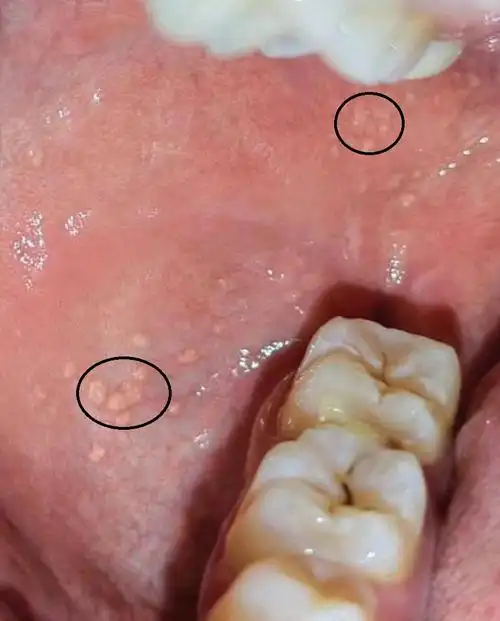

请大家帮忙,帮我看看,这是迷脂症还是口腔白斑?